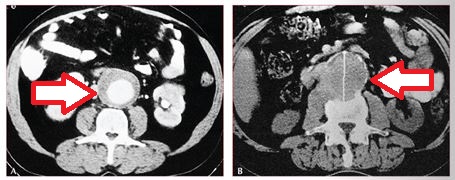

Hastalığın tanısı nasıl konur?

Bu hastalıkta en korkulan durum karın içindeki bu anevrizmanın yani baloncuğun yırtılmasıdır. Bu nedenle hasta kesinlikle doktorun takibinde olmalıdır. Hastanın tansiyonu kontrol altına alınmalı, kullanıyorsa kan sulandırıcı ve aspirin tedavileri kesilmelidir. Hastanın anevrizma çapı ultrason ve/veya bilgisayarlı tomografi ve/veya emar tetkiklerinde ölçülmelidir ve kayıt edilmelidir. Eğer anevrizma çapı 5 cm in üzerinde ise veya yılda 0.5 cm in üzerinde çapta artış varsa artık anevrizmanın yırtılma riski çok arttığından anevrizmaya yönelik girişim yapılmalıdır. Bu girişim 2 şekilde yapılır: